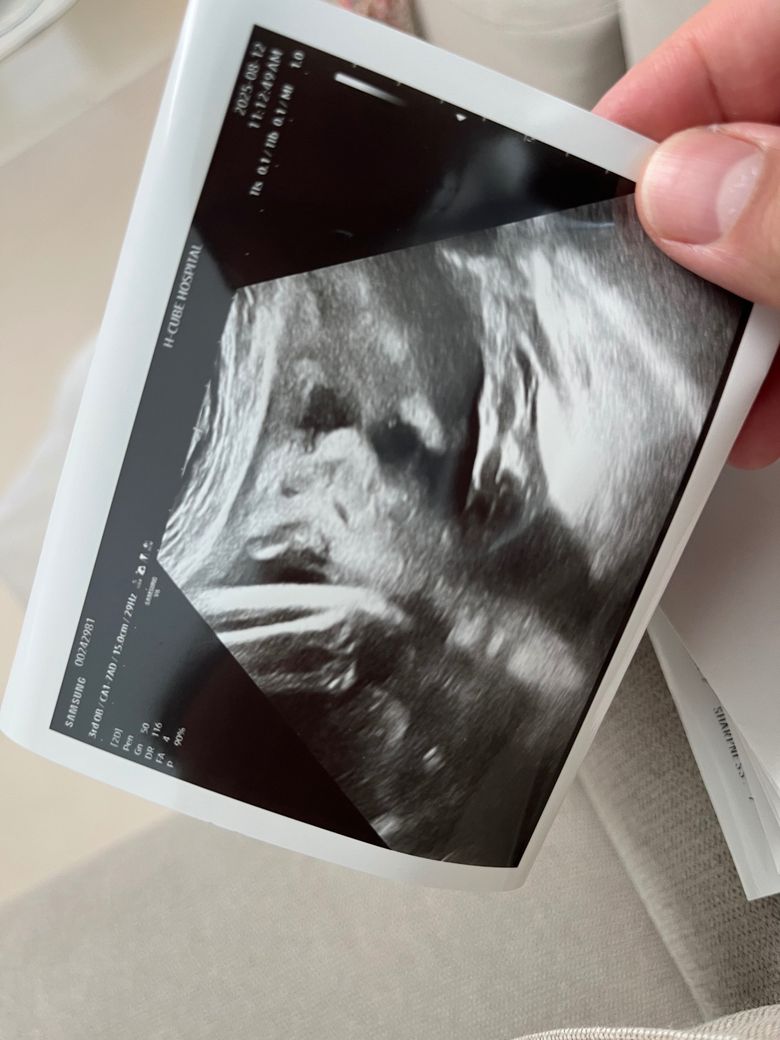

안녕하세요, 사진 순으로 24주차 입체초음파, 그 다음 두 장은 36주차 일반 초음파 사진입니다.

다름이 아니라 36주차 사진상 아이 눈 간격이 너무나 좁아보여서 걱정이 되어서 여쭈어봅니다..

옆으로 눌린 자세라 일시적으로 그렇게 보일 수 있는건지, 아니면 실제 저렇게 눈 간격이 좁은 아이의 경우도 있는지 궁금합니다.